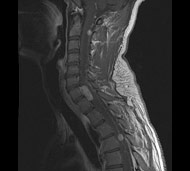

Спинальна магнітно-резонансна томографія (МРТ). Замість радіаційного випромінювання в МРТ використовуються потужні магнітні і радіохвилі для отримання зображення поперечного перерізу хребта. МРТ чітко відображає спинний мозок і нерви і забезпечує краще зображення пухлин кісток, ніж комп'ютерна томографія (КТ). Вам можуть ввести в вену кисті або передпліччя контрастну речовину, яка висвітлює деякі пухлини. Крім цього, використовують сканери з високою інтенсивністю сигналу для виявлення невеликих пухлин, які можна не помітити.